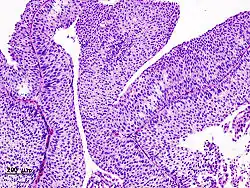

| Histopathology of transitional carcinoma of the urinary bladder. Transurethral biopsy. Hematoxylin and eosin stain. | |

The 1973 WHO grading system for transitional cell carcinomas (papilloma, G1, G2 or G3) is most commonly used despite being superseded by the 2004 WHO[14] grading for papillary types (papillary neoplasm of low malignant potential [PNLMP], low grade, and high grade papillary carcinoma). High-grade carcinoma typically displays more pleomorphism, multiple mitoses, euchromatin and relatively prominent nucleoli, and uneven distribution of nuclei.

Transitional cell carcinoma, being low-grade to the left, and high-grade to the right. H&E stain -

Papillary transitional cell carcinoma, low grade -